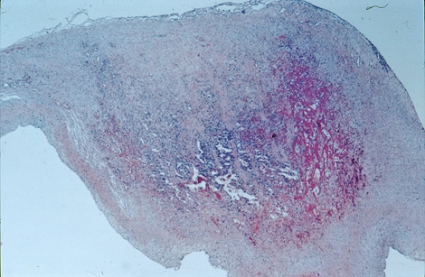

Figur 1 och 2 är PAD-bilder från mitralklaff från 2 av 14 kliniskt friska, 6 månader gamla grisar, som slaktades på vanligt sätt vid svenskt slakteri. Mitral- och trikuspidalklaffarna togs ut, och en del klipptes sterilt ner i transportmedium till bakteriologisk odling. Återstående del formalinfixerades, bäddades och färgades för mikroskopisk undersökning [2]. Inuti klaffarna fanns en anhopning av leukocyter (Figur 1), där streptokocker kunde framodlas hos 4 av 6 grisar.

Av avgörande intresse var att endotelbeklädnaden av såväl ovan- som undersida av klaffen var intakt och saknade ojämnheter, vegetationer eller andra förändringar på sin yta (Figur 1). Däremot fanns nekrotiskt material och granulationsvävnad inuti vissa av klaffarna, i vilka infektionen/inflammationen hunnit utvecklas längre. I detta mer framskridna infektionsskede hade även endokardiet på klaffytan börjat påverkas (Figur 2).